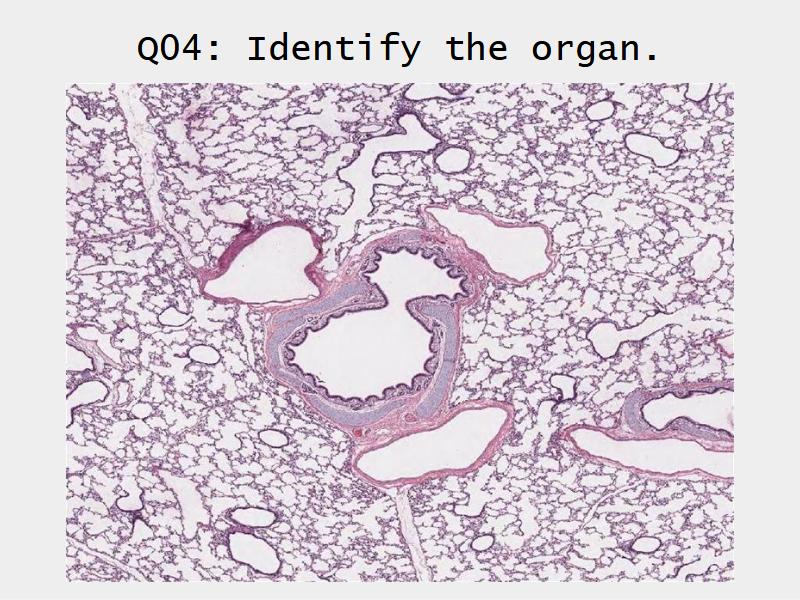

Slides: Respiratory System

- Slide 72 & 74: Lung

Lungs